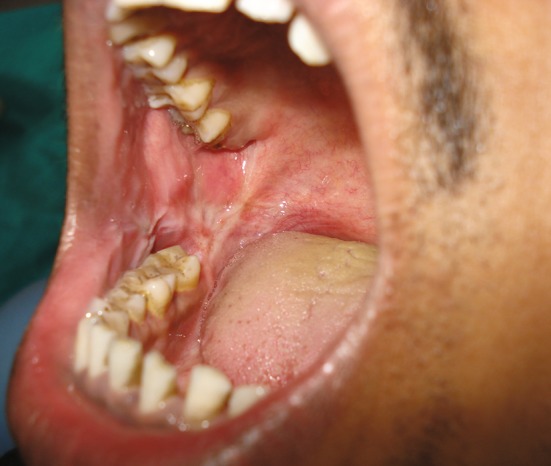

Fig. 5.

Twelve months post operative shows no signs of recurrence